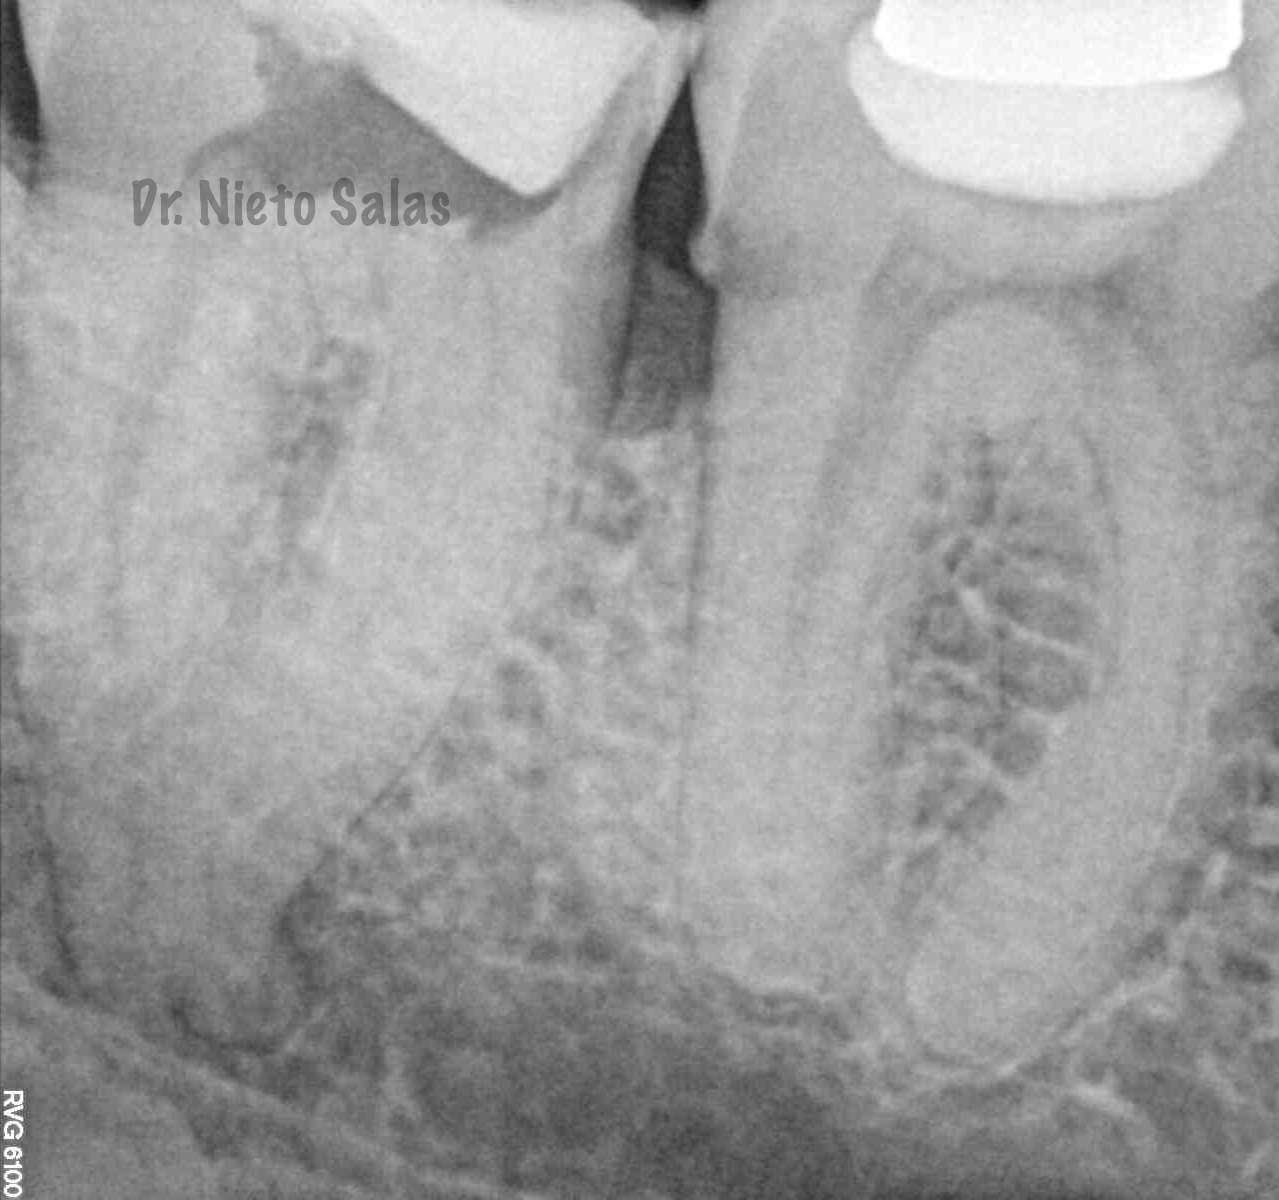

(buscamos siempre algún conducto lateral, para intentar asegurarnos de su limpieza)

Y una en las demás proyecciones MESIO Y DISTO: